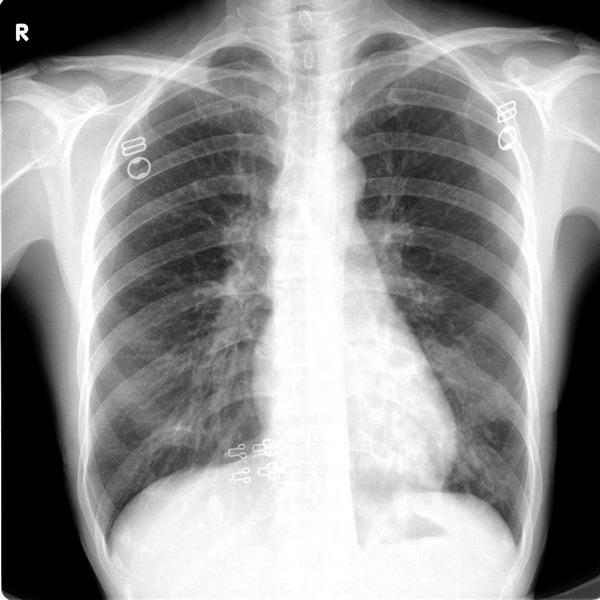

女 40y 咳嗽发热数月。

鉴于有的战友好象没怎么在意观察心影后,又调了一张传上来.

双下肺文纹理增多,左下肺似见有片状模糊影,考虑支气管炎伴有左侧肺炎。

左下肺可见片状影,密度不均,边缘模糊.建议ct检查.

左下肺尖端朝向肺门的三角形阴影,密度均匀,边缘清楚,考虑肺段不张,建议ct检查

左下肺片状模糊影,似可见空气支气管征,考虑肺炎!

双侧肺纹理增强,左下肺野见斑片状增密不均影,以心后区为明显。结合病史--女 40y 咳嗽发热数月。考虑肺部感染[警惕肺结核]。建议结合临床及ct检查

左下肺野内中带示斑片状密度增高影,其内示囊状影,部分囊内似有液平,心影重叠为著,考虑支气管扩张并肺感染。

双肺纹理增多,双下肺纹理呈网格状改变,左心后缘见数个囊状透亮影,结合临床考虑1.肺囊肿合并感染,2.支扩合并感染(患者没有咳血丝痰),建议ct扫描

左下肺(心影后)可见多个囊状影,壁稍后,部分囊内可见液平,考虑:左下肺支扩伴感染

双侧肺纹理增强,左下肺野见斑片状增密不均影,以心后区为明显。结合病史--女 40y 咳嗽发热数月。考虑支扩肺部感染。建议结合临床及ct检查